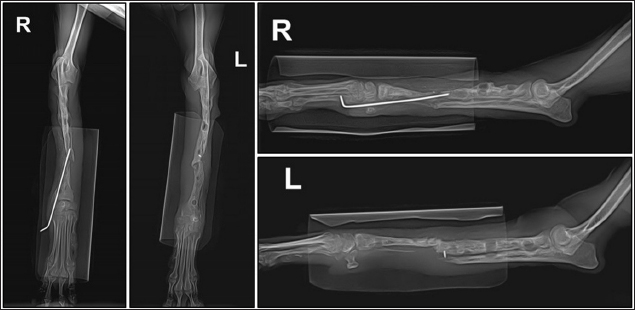

A two-step surgical plan was developed for managing the fractures. The remaining pin was removed in the first surgery and a CEF was applied for temporary fixation (Fig. 2A and B). Pins used included two 0.9 mm K-wires placed proximally and distally in a crossed manner, and one 1.2 mm olive wire placed in a single location. Anticipation of bone regeneration around areas of bone lysis near screw holes, and physical rehabilitation focused on inducing forelimb use until the second surgery. During the 6-week maintenance period of the temporary external fixation device, partial bone regeneration was observed in some areas of bone loss (Fig. 2C and D). Although forelimb ambulation remained plantigrade, there was an improvement in utilizing the limb smoothly with weight-bearing. In the second surgery, the CEF device was removed, and a surgical approach was made to apply the bone plate. The atrophied fracture sites on both sides showed no signs of bone regeneration and were partially debrided to expose the bone marrow cavities. The fracture was then fixed with a long bone plate and 1.5 mm screws. Autografts were harvested from the iliac wing and transplanted around the fracture site. This procedure was performed identically on both limbs with the fascia and skin closed in a standard manner. Additionally, CEF methods involved applying 0.9 mm K-wires, the same size as those used in the first surgery, above and below the plate on the fractured radius to provide further stability (Fig. 3).

Preoperative medications for both surgeries included tramadol (5 mg/kg, IV), cefazolin (30 mg/kg, IV), famotidine (0.5 mg/kg, IV), and midazolam (0.2 mg/kg, IV). General anesthesia was induced with propofol (5 mg/kg, IV) and maintained with 1.5%–2% isoflurane in oxygen. Intraoperative analgesia was provided by a constant-rate infusion of ketamine and lidocaine. The forelimbs were then prepared for routine aseptic surgery. The entire surgery lasted 2 hours and 50 minutes. Postoperatively, cefazolin was administered for 5 days, along with tramadol and meloxicam (0.1 mg/kg, SC) for pain management. Amoxicillin syrup was prescribed for an additional 3 weeks as an antibiotic. Sutures were removed in the second postoperative week, and ongoing physical rehabilitation was implemented. External fixation devices were removed in the fourth postoperative week. Radiographic assessments showed a union of the right radius by the eighth postoperative week and the left radius by the tenth postoperative week (Fig. 4). Although forelimb ambulation remained plantigrade, the dog’s overall gait improved, enabling consistent quadrupedal movement.

Fig. 3. Lateral radiograph of bilateral radius and ulna fracture reduced using circular external fixation along with plate and screw fixation.

Fig. 4. Lateral radiograph 10 weeks after the second surgery showing bone union progression.

Previous studies have highlighted challenges in using external fixation in toy-breed dogs due to their size, particularly in the radius (Hamilton and Langleyhobbs, 2005). However, based on the author’s clinical experience with successful CEF applications, this study initially applied CEF for temporary fixation to promote the reconstruction of lysed bone and stabilize surrounding soft tissue. Rehabilitation was performed to maintain joint function, promote vascularization, and enhance muscle mass until a second surgery was conducted. Although radiographic evaluation revealed no signs of union at the fracture site, the frequency of forelimb use increased after temporary fixation. Six weeks after the first surgery, radiography showed increased bone thickness and a decrease in the areas of lysis. In the second surgery, the fracture was reduced using plates and screws, and CEF was applied simultaneously for 4 weeks. During the 10 weeks of CEF application, no complications such as infections or implant loosening were observed, and it provided the necessary stability to maintain alignment and regenerate the bone.